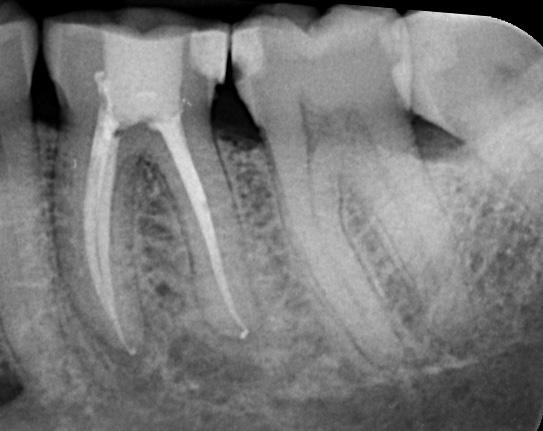

The purpose of the root canal procedure is to remove the inflamed tissue or bacteria inside the root canal and thus allow the supporting tissues to heal. After cleaning the root canal system, the space created is filled with a root filling, using a rubber material called gutta-percha.

Step 3: Filling and Sealing Once cleaned, the root canal system is filled with a root filling, typically using a rubber material called gutta-percha. For cases with long-standing infection, anti-bacterial medicaments may be placed inside the canals between visits to kill any remaining bacteria, sealed by a temporary filling for about one week.